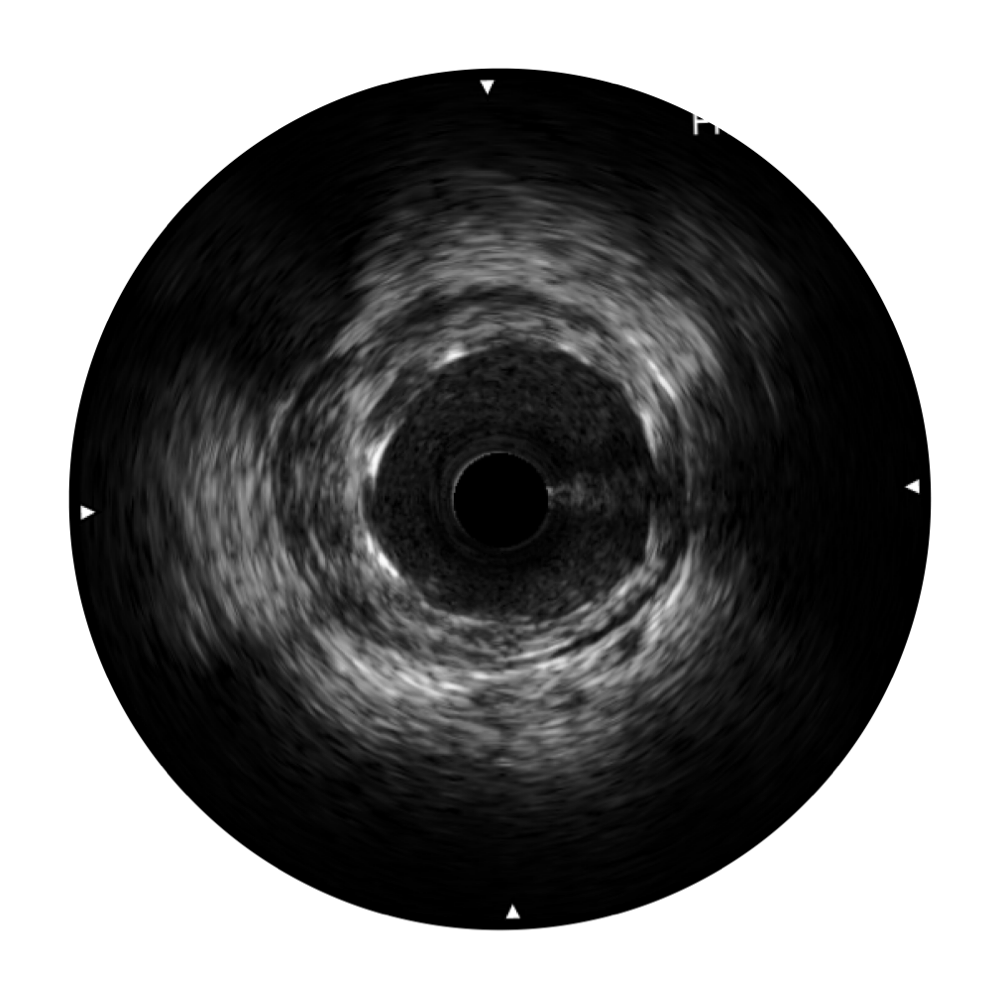

• 传统IVUS图像

对比传统IVUS导管成像,哈哈体育官网宽频IVUS图像的近场支架梁显影更细腻,远场中膜外血管仍清晰可辨,兼顾远中近,兼顾分辨力与穿透深度